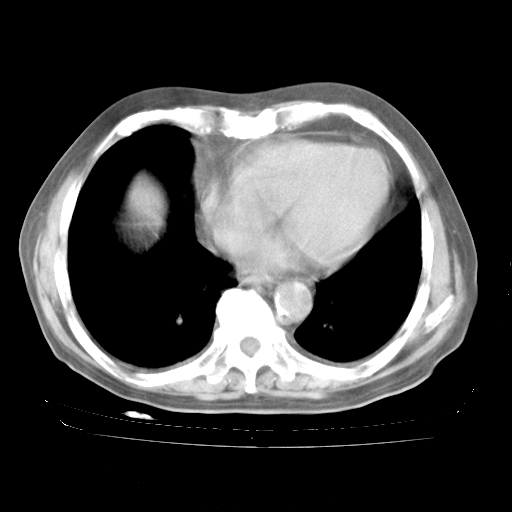

今天部分检查

轻微咳嗽,无痰,(体温正常时)R20次/分,P75次/分,双肺底、腋下可闻及少量捻发音。下肢轻度浮肿。

血常规:白细胞9.11×109/L,N0.92,L5.64,血小板39.2×109/L,HB148g/L,ESR2mm/H。

尿常规:潜血+

血生化:总蛋白69.71g/L,白蛋白38.40g/L,球蛋白31.31g/L,CRP27.9mg/L,尿素氮11.98mmol/L,肌酐106μmol/L,乳酸脱氢酶1099 U/L,肌酸激酶108U/L,CK-MB 61U/L。

腹部B超:胆囊壁增厚,肝、胆、胰、脾、肾无异常,肠系膜淋巴结、腹膜后淋巴结无增大。

ECG:右心室增大

心脏超声检查:无右心室增大。

增加治疗:异烟肼、利福平、乙胺丁醇,静滴左氧氟沙星、参麦注射液。甲强龙从80mg暂减为40mg。

强的松3月1日改为10mg qd,4月1日改为10mg qod。3月份以前的减量过程和环磷酰胺疗程需等明天查看记录(我岳父自己做的记录在他家里)。